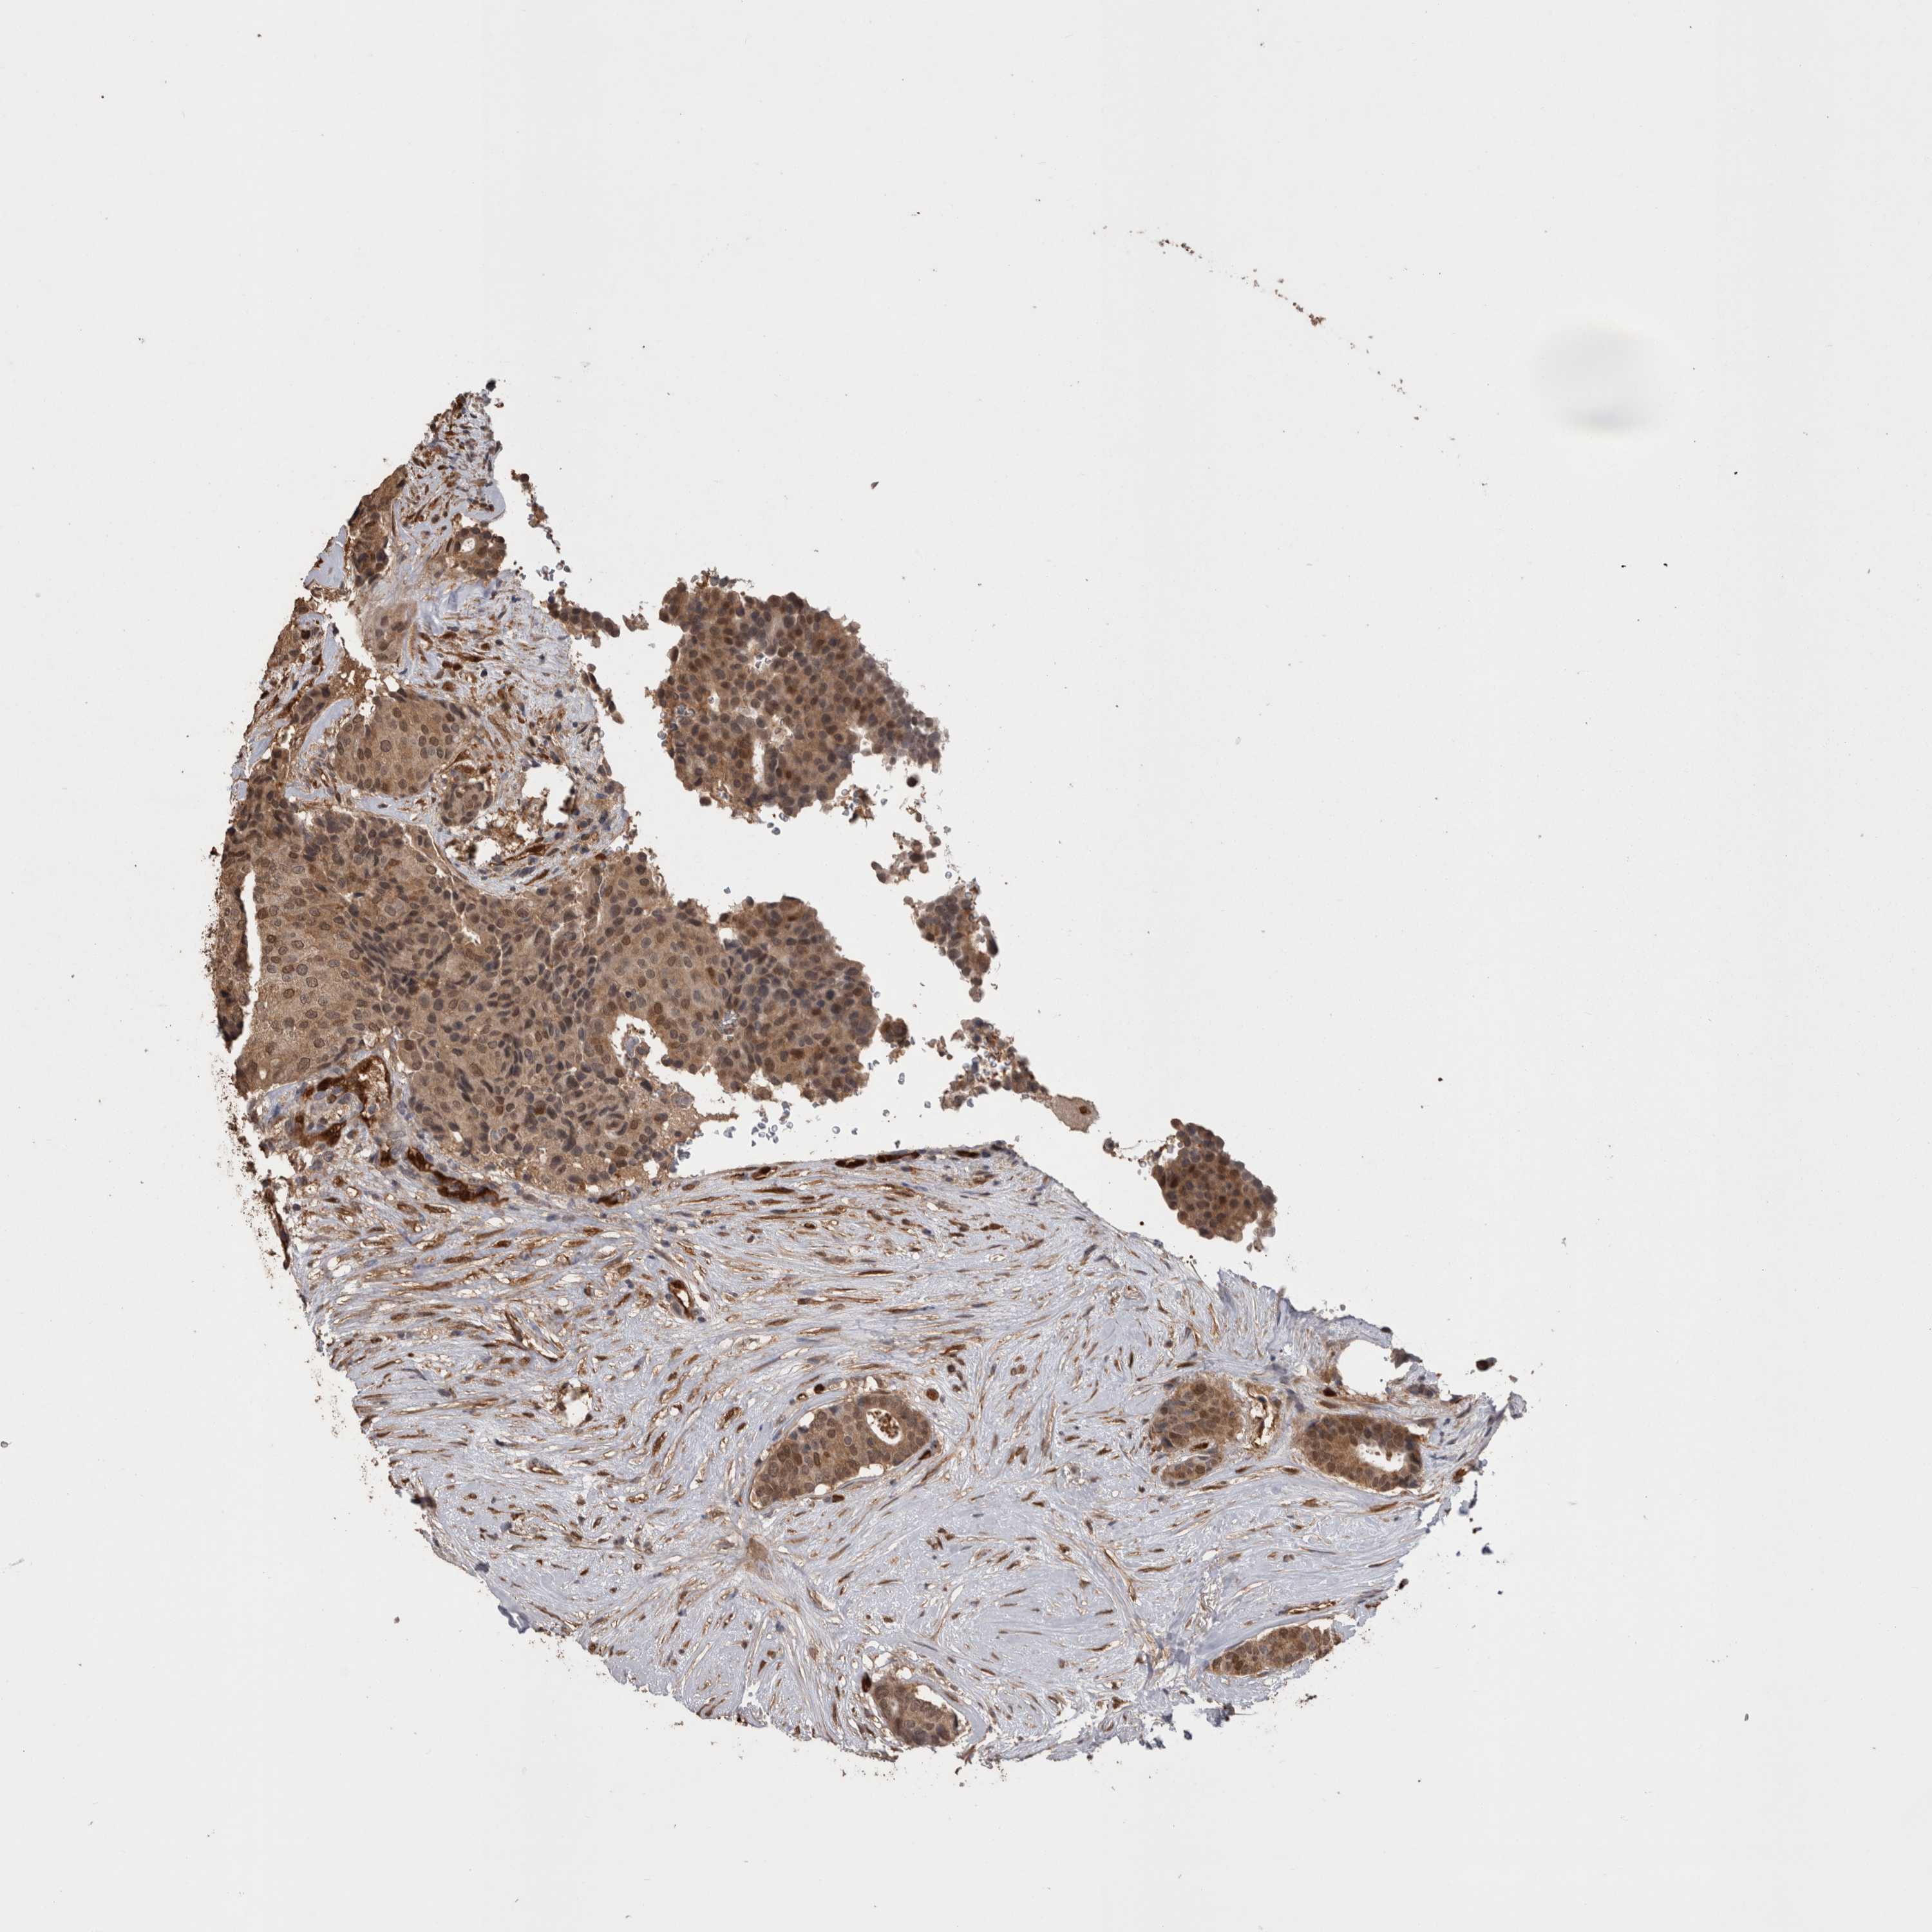

CANCER BREAST CANCER Show tissue menu

BRCA TCGA BRCA VALIDATION PROTEIN EXPRESSION